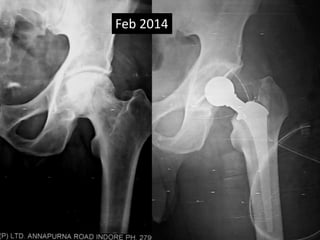

• 54 years old Female

• AMP done out side.

• Had acute onset of anterior thigh pain May 2012.

• A suggestion was given to for Total Replacement

out side.

• Seen May 2012 with Broken Stem

• Full range free movements at hip

• Last seen Dec 2012.

Feb 2010

May 2012

Dec 2012

Lateral cortical

Hypertrophy